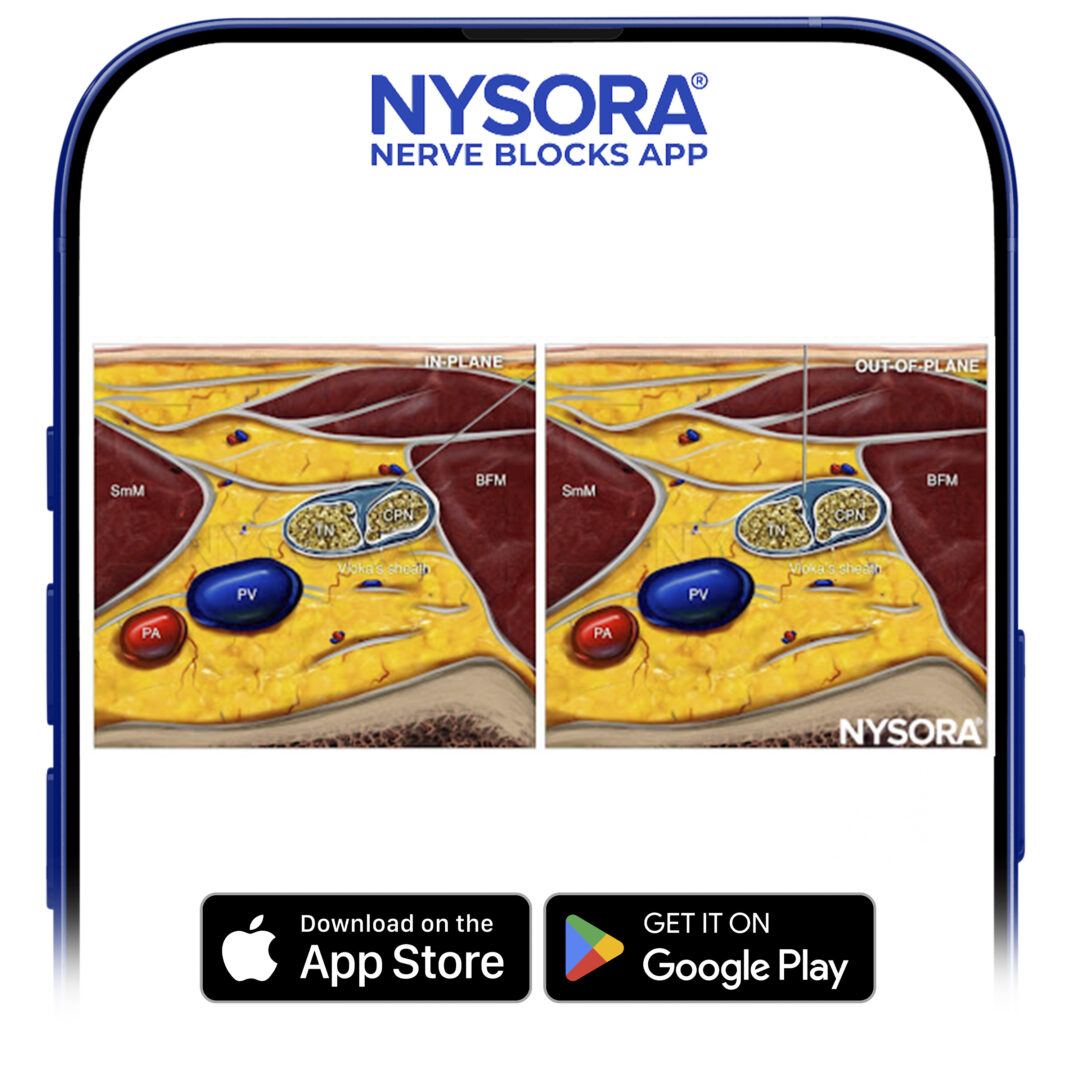

Reverse Ultrasound Anatomy for a popliteal sciatic nerve block with needle insertion in-plane and out-of-plane and local anesthetic spread (blue). TN, tibial nerve; CPN, common peroneal nerve; PV, popliteal vein; PA, popliteal artery; SmM, semimembranosus muscle; BFM, biceps femoris muscle.